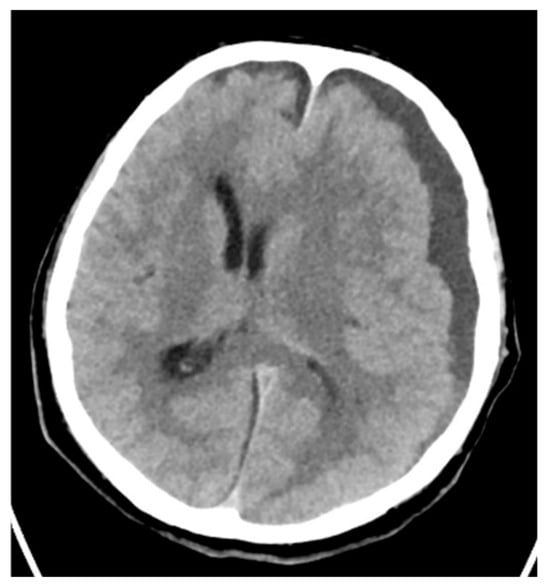

| 4 | 67/M | Otitis media Cerebral abscess | Hypertension Gastroesophageal reflux disease | no | 23 | 13 | yes | 27 days | Discharge |

| 4 | No | antro-mastoidectomy abscess evacuation | blood culture ear discharge | Ampicillin Ceftriaxone Metronidazole Vancomicin | Penicillin Clindamicin |